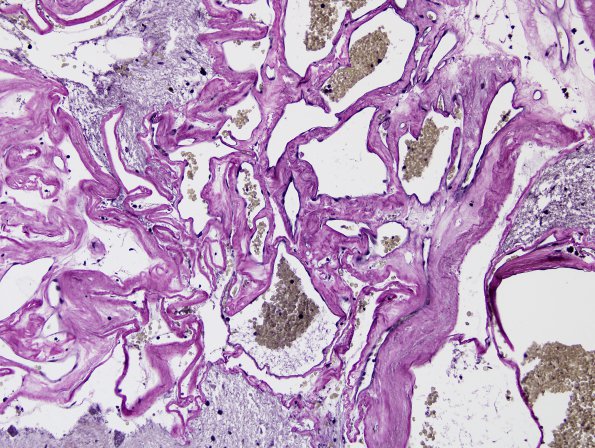

22D2 Cavernous angioma (Case 22) VVG 1

Vascular channels do not include arterial elements as seen by this elastin stain (Elastin)